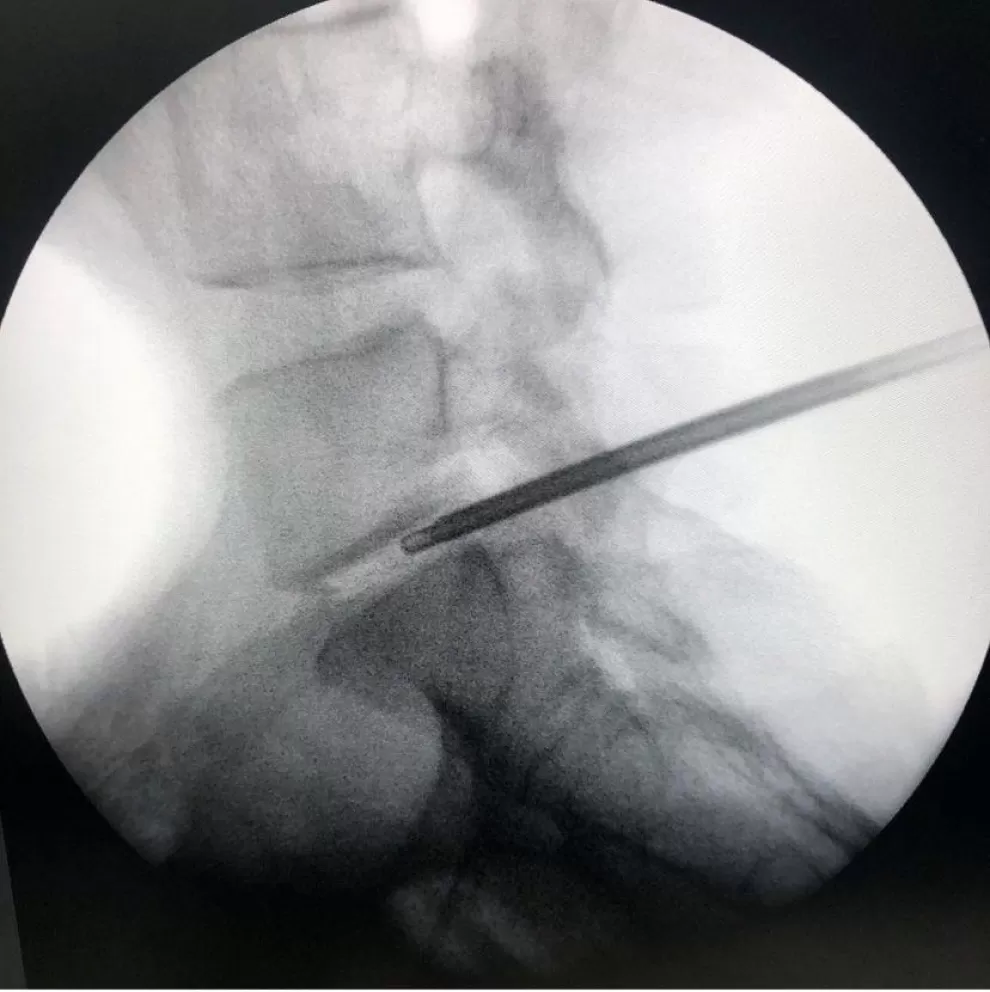

A Discectomia percutânea é um procedimento minimamente invasivo para tratamento de hérnia de disco lombar. É realizada em centro cirúrgico, com sedação e anestesia local, utilizando-se uma cânula para acessar o disco intervertebral. Dessa forma, a hérnia de disco é retirada através de corte e aspiração com essa cânula. O paciente geralmente recebe alta no dia seguinte.